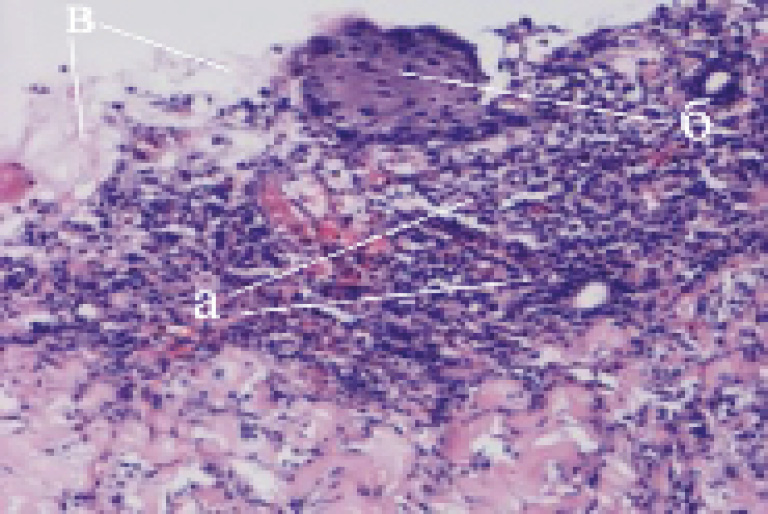

При микроскопии гистологических препаратов из ожоговых ран, через неделю после НЭ и трансплантации культуры ФФбл выявляются различия в морфологическом строении исследуемого и контрольного участков. На исследуемом участке появляется грануляционная ткань, небольшие островки эпидермиса при сохраняющейся инфильтрации нейтрофильными лейкоцитами, что подтверждает процесс гнойного воспаления в ране (рис. 2).

Рис. 2. Микроскопический вид биоптата из ожоговой раны через 7 суток после трансплантации ФФбл: а – грануляционная ткань; б – формирующийся эпидермис; в – нейтрофильная инфильтрация. Окраска гематоксилином и эозином, ув. ×30